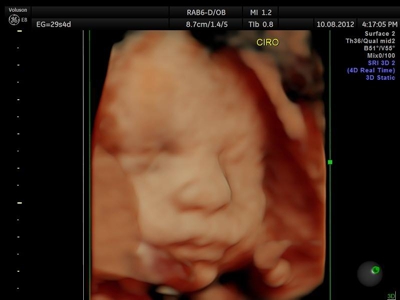

Fotografías de ecografías 4D HD/5D

Haga click sobre las imágenes para ampliar